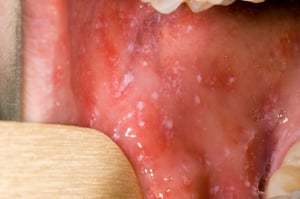

Kabla ya upele kuanza, madoa ya Koplik huenda yakaonekana ndani ya mdomo. Madoa ya Koplik ni madoa madogo mekundu angavu yenye sehemu nyeupe au bluu. Sehemu za katikati zinaweza kufanana na chembe za mchanga.

Madoadoa yanayotambuliwa kabla ya kuanza kwa upele ni madoadoa mekundu angavu yenye sehemu za kati zilizo na rangi nyeupe au bluu ambayo yanaweza kufanana na chembe za mchanga. Yanaweza kutokea popote mdomoni kwa watu walio na surua.

Picha kwa hisani ya Maktaba ya Picha ya Afya ya Umma ya Vituo vya Kudhibiti na Kuzuia Magonjwa.